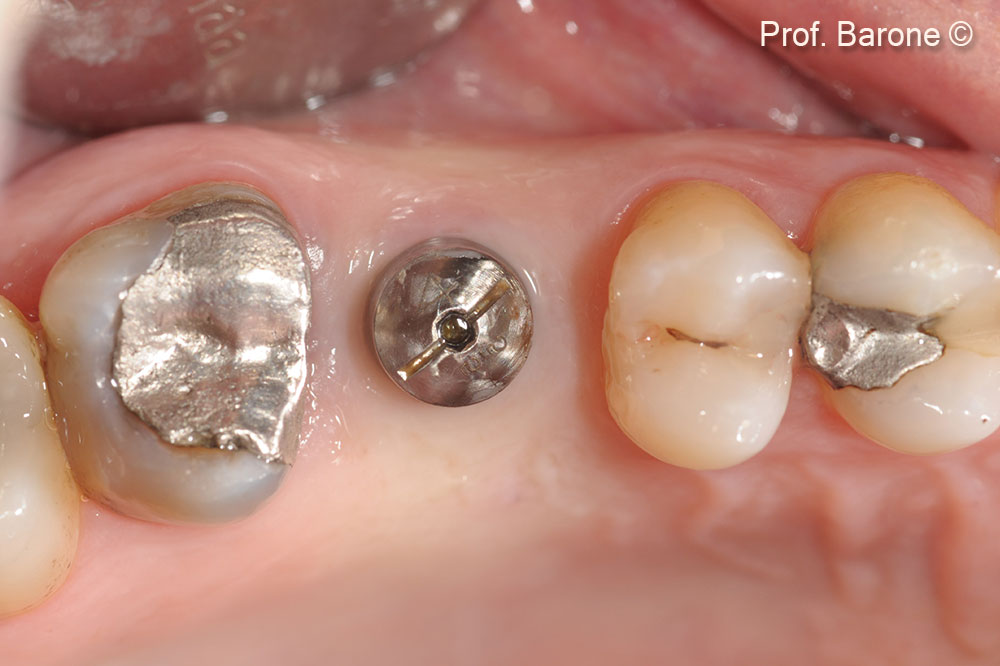

Trụ lành thương, nhìn từ mặt nhai